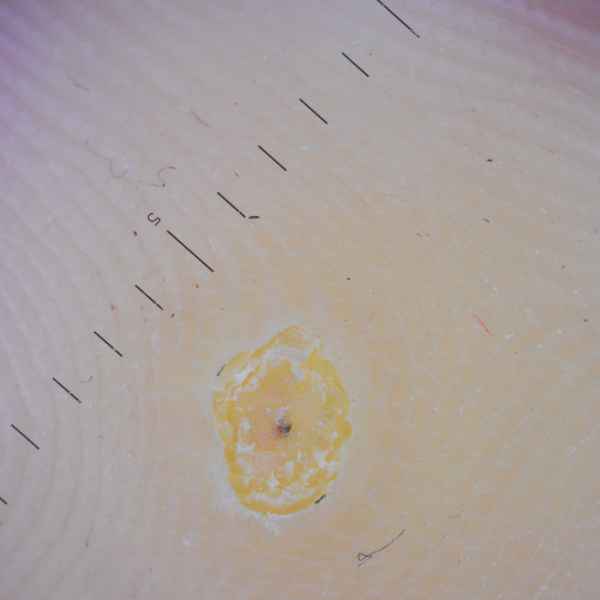

Бородавка подошвенная